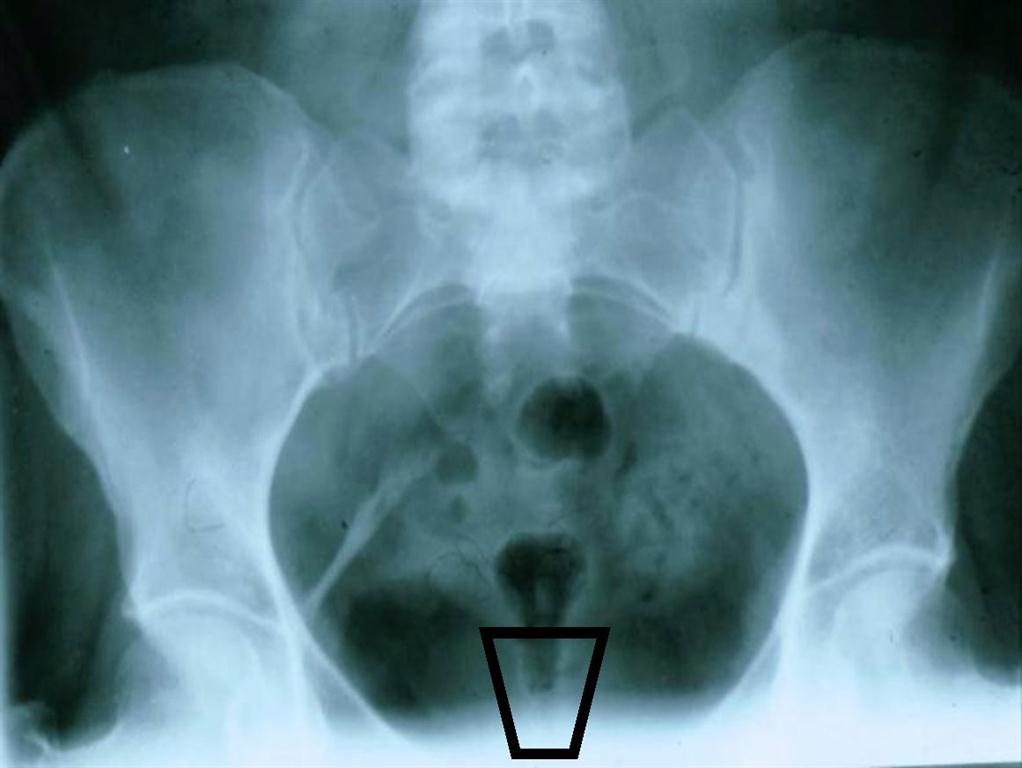

COCCYGEAL AREA